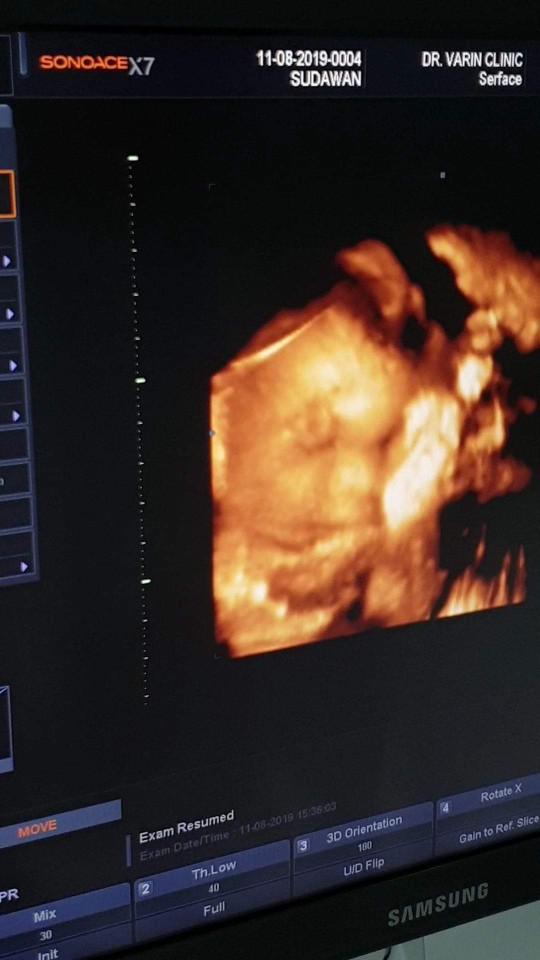

อวดรูปลูกตอนซาวด์ 4 มิติค่า

สวัสดีค่ะแม่ๆ หนูอยู่ในท้องคุณแม่ 7 เดือนนะคะ

ซาวตอน27วีคค่ะ